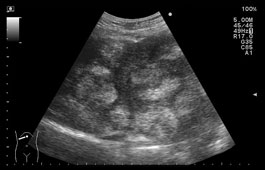

・転移性肝腫瘍:クラスターサイン

「クラスターサイン」は、転移性肝腫瘍に特徴的な所見です。これは多数の腫瘍が増大し、ぶどうの房のように融合して一塊となり描出される状態を指します。このサインは、多発性の腫瘍が集簇していることを示し、しばしば転移性肝腫瘍の診断に有用とされます。